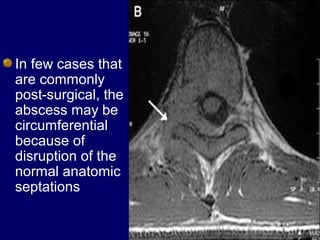

In few cases that

are commonly

post-surgical, the

abscess may be

circumferential

because of

disruption of the

normal anatomic

septations